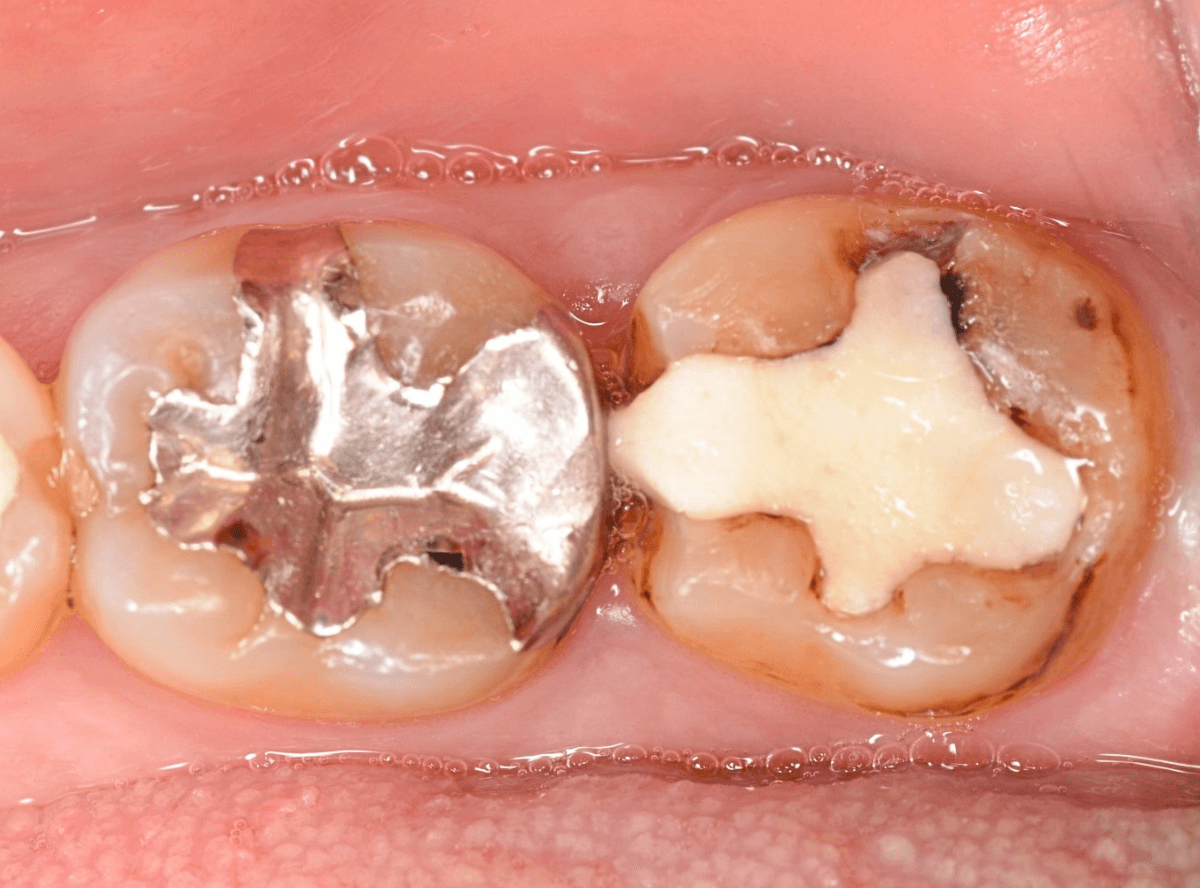

メタル・インレーとメタル・クラウンが入っていますね。

まずは、奥のメタル・クラウンを外します。

メタル・コアが入っていますが、こちらも慎重に外して、中を調べていきます。

レントゲン写真では問題なさそうでしたが、メタルコアを除去すると、中は真っ黒でした。

このように、コアの中で虫歯が進行している場合もありますので、さし歯をやり直す際は、出来る限りコアも外して調べるようにしています。